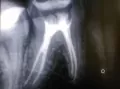

• К сожалению, с онемением я Вам помочь не могу. Это все будет видно через месяц-полтора, а что касается лечения зуба, по снимку видно, что зуб пролечен, в принципе, неплохо. Но, рекомендую сделать ещё один прицельный снимок, либо сделать К/Т зуба. После этого можно будет поставить точный диагноз и дать Вам рекомендации.